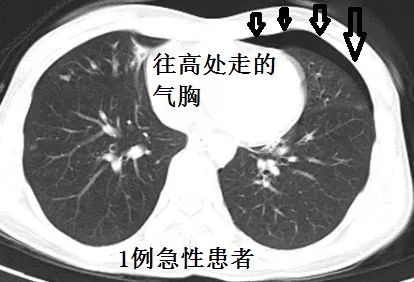

前不久会诊,遇到一个患者,CT如下:

平卧位,主动脉弓层面,没有气胸

隆突层面,少量气胸

中叶支气管层面,气胸增多

膈肌层面,气胸更多

仔细看看,这个患者的脏层胸膜增厚,提示气胸很可能不是近期的事情,很可能是长时间造成的,正常的肺表面不会有增厚的、白色的一圈。

追问病史,患者诉没有任何呼吸系统症状,气胸是偶然发现的。很明显,这个患者要考虑慢性气胸。

CT如下: